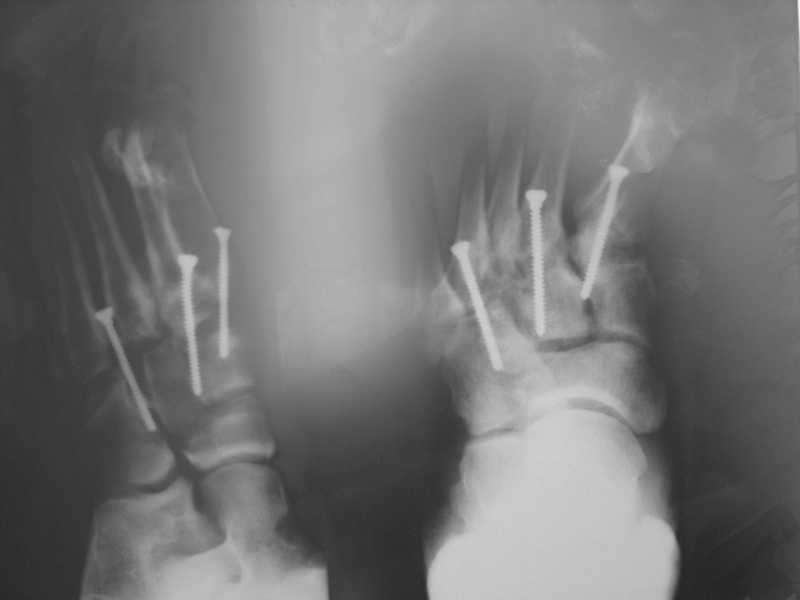

Здравствуйте , уважаемые коллеги. Обратился пациент, мужчина 42лет. для дальнейшего

лечения. Травма 11.09., ДТП.

15.09 проведено оперативное лечение (Блокирующий стержень левого

бедра - статическая система. Открытое вправление вывиха в суставе

Лисфранка и фиксация мет. фиксаторами.)

D.S. Переломы диафиза и межмыщелковой области левого бедра, вывих в

суставе Лисфранка правой стопы. Состояние после МОС. Через 6 нед.

контрольная Ro, (снимки прилагаются).

По суставу Лисфранка : 1- 8 -9 нед . полный покой в гипсовой шине,а

потом дозированная нагрузка. 2- Сейчас (на 7 нед.) пригипсовать

каблук под пятку и давать дозированную нагрузку, и на 12 нед,

одновременно с  переводом статической системы в динамическую провести

удаление фиксаторов из стопы. Какую тактику посоветуете Вы?.